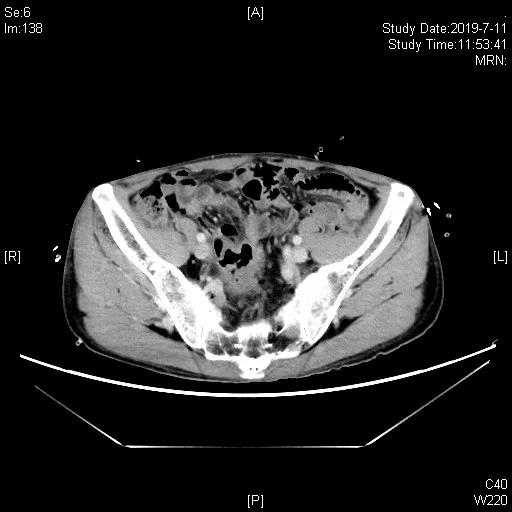

一线治疗:2019-05-21 “吉西他滨1.2d1,d8+卡铂500mgd2”化疗1周期,06-17 “吉西他滨1.4d1,d9+奥沙利铂200mgd2”化疗1周期。07-12胸腹部CT及盆腔MRI评估近期疗效为完全缓解(CR)。于07-12至10-05共计“吉西他滨1.4d1,1.2d14+奥沙利铂200mgd2”化疗4周期,III°血小板减少及白细胞减少,影像学评估CR。11月底出现造瘘口出血, 11-30胸腹部CT示回肠代膀胱壁增厚伴软组织肿块,考虑再次复发。

2019.7.11一线化疗2周期后